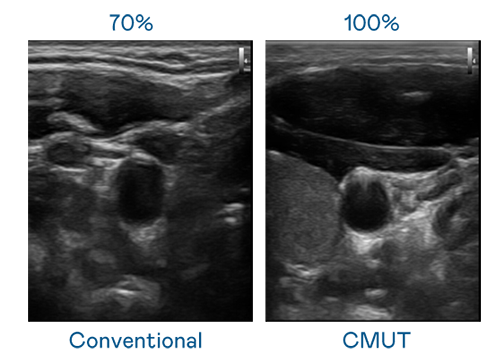

CMUT 技术是一种用电容式微机电元件来产生超音波讯号的技术。与传统 PZT 压电式技术相比,CMUT 频宽增加 30%,更宽频的超音波讯号让影像解析度大幅提升,是实现高影像品质医疗超音波扫描、促进精准医疗发展的关键技术。

大频宽带来超清晰影像

超音波影像的解析度高低,首先取决于探头能发出的讯号频宽。Z6尊龙 CMUT 可提供高清晰的超音波讯号,提供高频宽、高灵敏度、影像纹理细节更高的超音波影像,协助医护人员缩短影像判读时间及利用精准的医疗影像进行诊断。